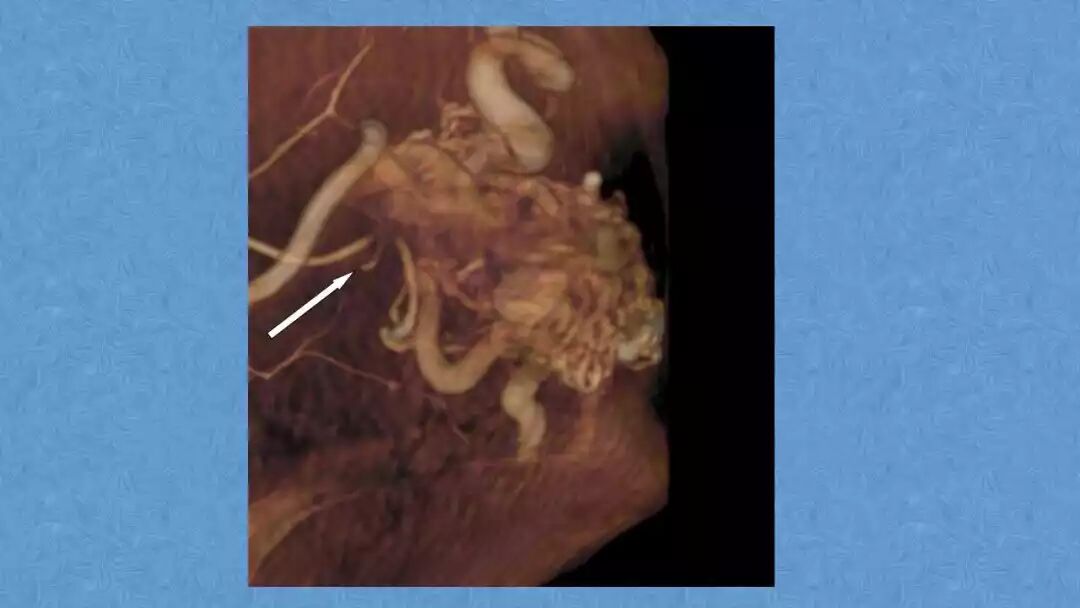

今天为大家分享的是《贝朗时间》第二十九期,湖北十堰市太和医院神经外科张力教授团队带来的:一个AVM患者的48小时纪实,欢迎阅读、分享!

张力教授:AVM切除术